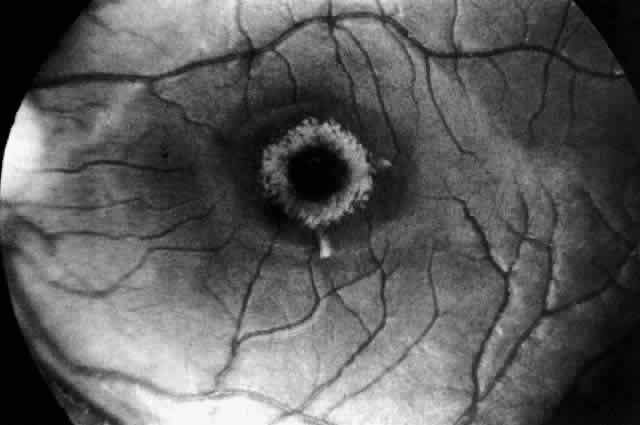

Niemann-Pick Disease Type B. A unique retinal abnormality, the macular halo syndrome has been reported in seven cases of Niemann-Pick disease type B, three enzymatically proven52–54 and four prior to enzyme verification described between 1950 and 1970.55–58 Symmetrical punctate crystalloid ring-form opacities about the foveas were observed in each case with no visual impairment. Cogan and Federman56 in one of the early cases were the first to publish a fundus photograph of the macular halo (Fig. 6). The patient was a 24-year-old woman with hepatomegaly, no neurologic signs, and a reticuloendotheliosis of unclassified type. Both fundi showed doughnut-shaped opacities about the foveas. The opacities were described as yellowish white scintillating granules forming a relatively sharp border on the inner edge of the ring and a ragged border on the outer edge of the ring. Despite this condition the patient had normal visual acuity (20/15 [6/5]) and no scotoma.

Fig. 6. Fundus of patient with Niemann-Pick disease type B showing the macular halo syndrome. (Cogan DG, Chu FC, Barranger JA, Gregg RE: Macular halo syndrome; variant of Niemann-Pick disease. Arch Ophthalmol 101:1698, 1983. Copyright © 1983, American Medical Association)

The first case verified enzymatically was reported by Harzer and associates in 1973.52 The assay showed a sphingomyelinase level in leukocytes that was less than 10% of normal.

Although these scattered reports were in the literature, it was Cogan who clearly identified the lesion and made the association with Niemann-Pick disease type B. Cogan and co-workers53 reexamined their initial patient and added a 21-year-old man with a history of splenomegaly and hyperlipidemia. The diagnosis of Niemann-Pick type B disease in each of these patients was confirmed by finding significantly lower sphingomyelinase levels in cultured skin fibroblasts. They named the condition macular halo syndrome. In these cases, the opacities in the retina formed a halo approximately one-half disc diameter at their outer edge. The halo had a crystalloid appearance. By stereo-ophthalmoscopy, slit lamp biomicroscopy, and fluoroangiography the opacities appeared to occupy various depths of the retina but were most numerous in Henle's fiber layer, causing only minor obscuration of the overlying vessels.

The foveal lesion in Matthews and associates' patient54 is similar in size and appearance to the fundus photograph published by Cogan and coworkers. On the basis of stereo biomicroscopy and contact lens examination, Matthews and associates located the lesion in the ganglion cell layer of the retina. The masking effect that the ring lesion had on the perifoveal vasculature in the early fluorescence angiogram was taken as confirmation that the accumulated material is in this superficial layer of the retina. As a result, Matthews and associates proposed that the macular halo represents the smallest or mildest form of a cherry-red spot—findings in conflict with those of Cogan. The precise location of the opacities in the retina remains uncertain, however, because of the lack of histopathology.

The available clinical data suggest that such opacities are permanent. For example, the appearance of the macular halo remained unchanged for 15 months in one case,57 4 years in another,52 and more than 20 years in one of Cogan's cases.53 Cogan concluded that the remarkable preservation of normal visual function in all of the cases either was due to hiatuses in the opacities or, less likely, to a localization of the opacities behind the photoreceptors.